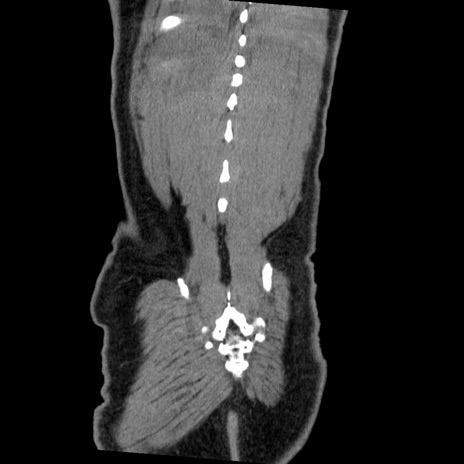

症例22(冠状断像)

【症例】50歳代男性

【主訴】腹痛

【現病歴】AVMからの被殻出血のため回復期リハ病棟入院中。 本日午後3時頃急に下腹部痛が出現した。

【既往歴】AVM、被殻出血、虫垂炎、高血圧

【身体所見】意識晴明、左半身不全麻痺、会話の理解は良好、36.5°C、腹部:膨隆、全体に板状硬、下腹部正中に圧痛点あり、反跳痛-、筋性防御不明、右下腹部にope scar

【データ】WBC 9400、CRP 0.06